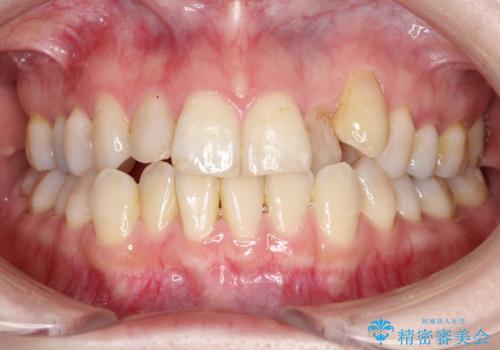

【がたつき・深い噛み合わせでお悩みの方必見】抜歯矯正症例(審美ワイヤー矯正)

初診時の歯並びの状態としては、上下ともに前歯部の中等度のがたつきがあり、下の前歯は本来生えるはずの歯が2本生まれつき欠損している状態でした。

また、上顎の歯は虫歯で歯冠が崩壊してしまって保存不可能な歯がありました。

抜歯ありワイヤー矯正にて治療を行い、抜歯する歯に関しては虫歯で抜歯が必要な部分を有効活用することで、健康な歯を保存するように努めました。

噛み合わせが深い過蓋咬合という状態でもあったため、下の歯の装置をつけたり、嚙み合わせを上げる(下の歯が見える状態にする)ことにたいへんに苦労した症例でした。